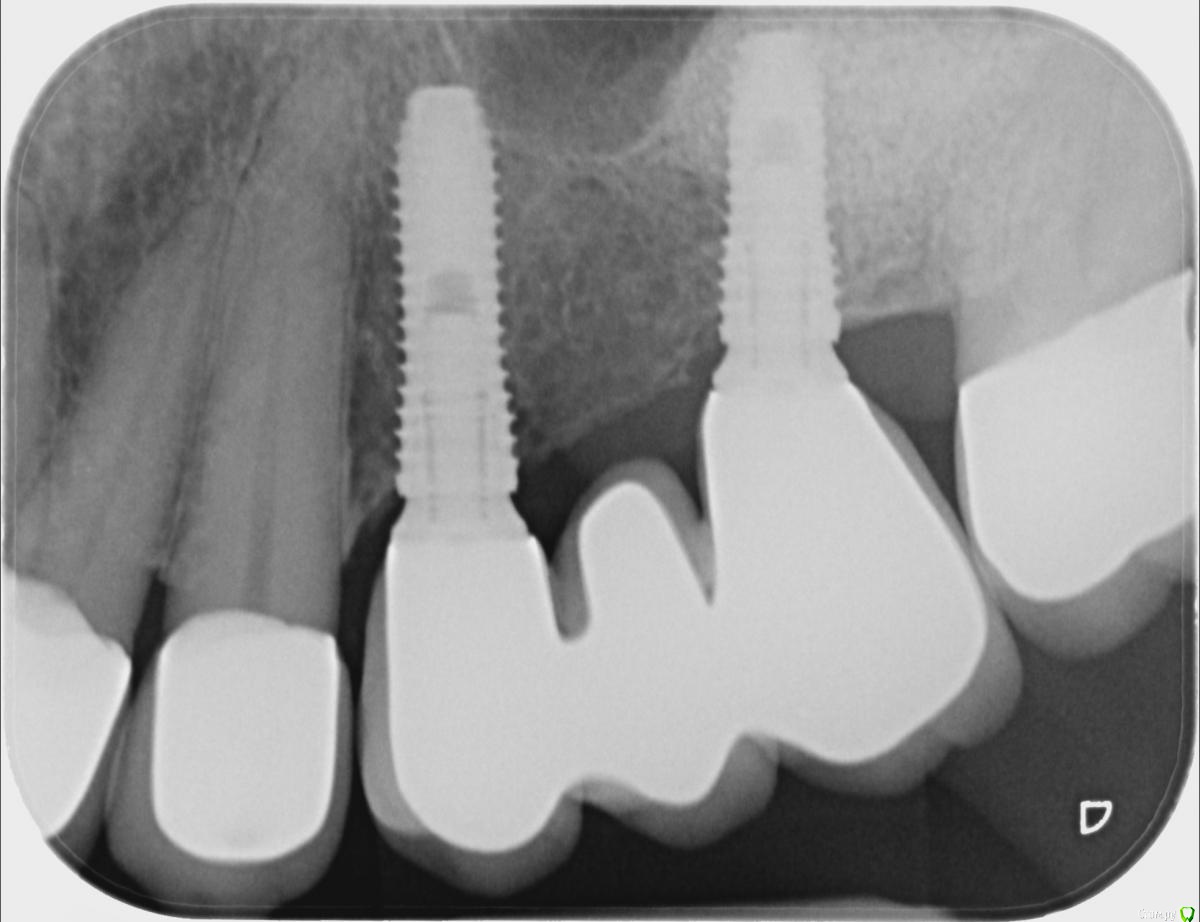

ellenchik Опубликовано 6 февраля, 2019 Автор Поделиться Опубликовано 6 февраля, 2019 Добрый вечер. Сделала сегодня прицельный снимок . Врач говорит,что проблема в имплантате. Она видит там воспаление. Прокомментируйте,пожалуйста, снимок. Спасибо! С уважением Елена Ссылка на комментарий

ellenchik Опубликовано 9 января, 2020 Автор Поделиться Опубликовано 9 января, 2020 Добрый день, уважаемые Доктора.Я снова к Вам за советом. После отпуска ( Перемена климата -прилетела из +25 в +2 град.) уже неделю болит уже другой передний зуб под коронкой (канал пролечен 4,5 г. назад) Болит очень высоко с внешней стороны десны в самом вверху. Особенно при нажатии точки прямо под правой ноздрёй носа. Боль жгучая,ноющая. С нёбной стороны никаких болевых ощущений. Временами такая "гуляющая" боль по передним верхним зубам. Врач сделал снимки и сказал, что надо делать резекцию верхушки корня у этого зуба и заодно у рядом стоящего зуба (по моему клык) с пролеченным каналом. Еще он где-то увидел трещину.В рот заглянул,но зубы ни на какие реакции не проверял. На снимках причинный зуб (по моим ощущениям ) с "кривым кружочком"Буду очень признательна за советы. Действительно все так плохо по снимкам и необходима резекция обоих зубов? Или есть другие варианты. И на каком зубе видна трещина? С уважанием ЕленаP.S-Прикрепляю на всякий случай старый снимок ( третий по счету ) этих зубов после лечения в 2015 г. Ссылка на комментарий